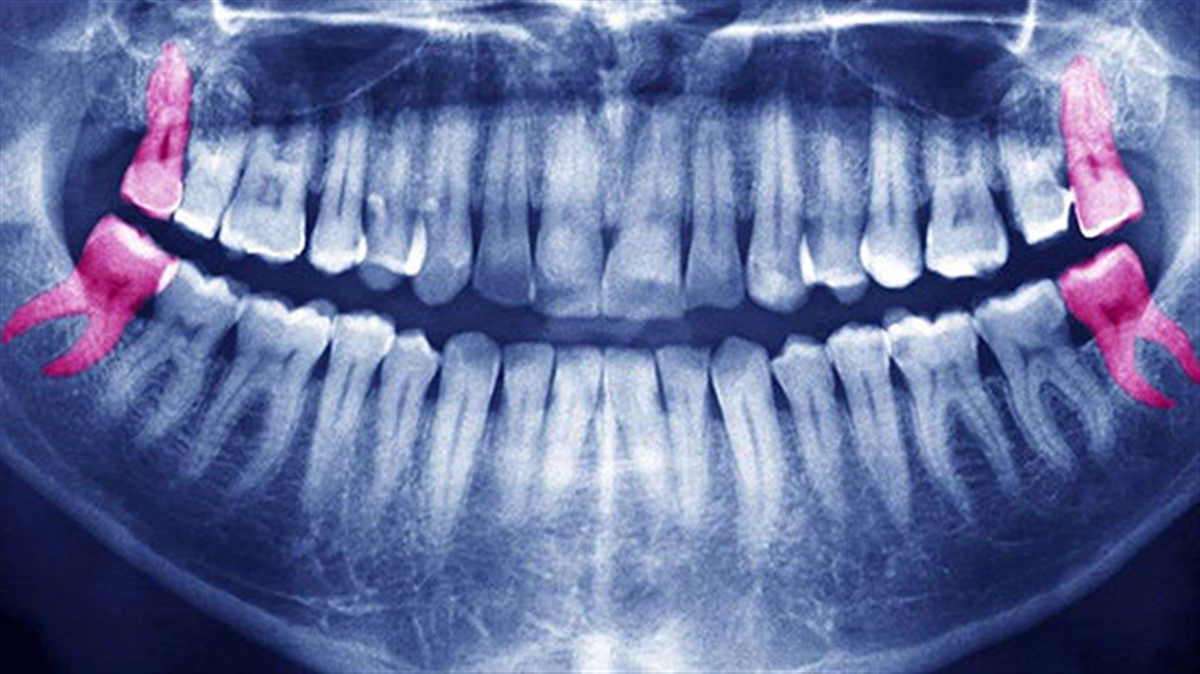

دندانهای عقل، آخرین دندانهای دائمی هستند که معمولا بین سنین ۱۷ تا ۲۵ در دهان ظاهر میشوند. دندان عقل در برخی افراد هرگز رشد نمیکند. بسیاری از افراد ممکن است دندان عقل نهفته داشته باشند؛ به این معنا که فضای کافی برای خروج این دندان وجود ندارد.

مشکلات ناشی از دندان عقل نهفته

اگر دندان عقل نهفته منجر به مشکلات زیر شود، بهتر است آن را بکشید: